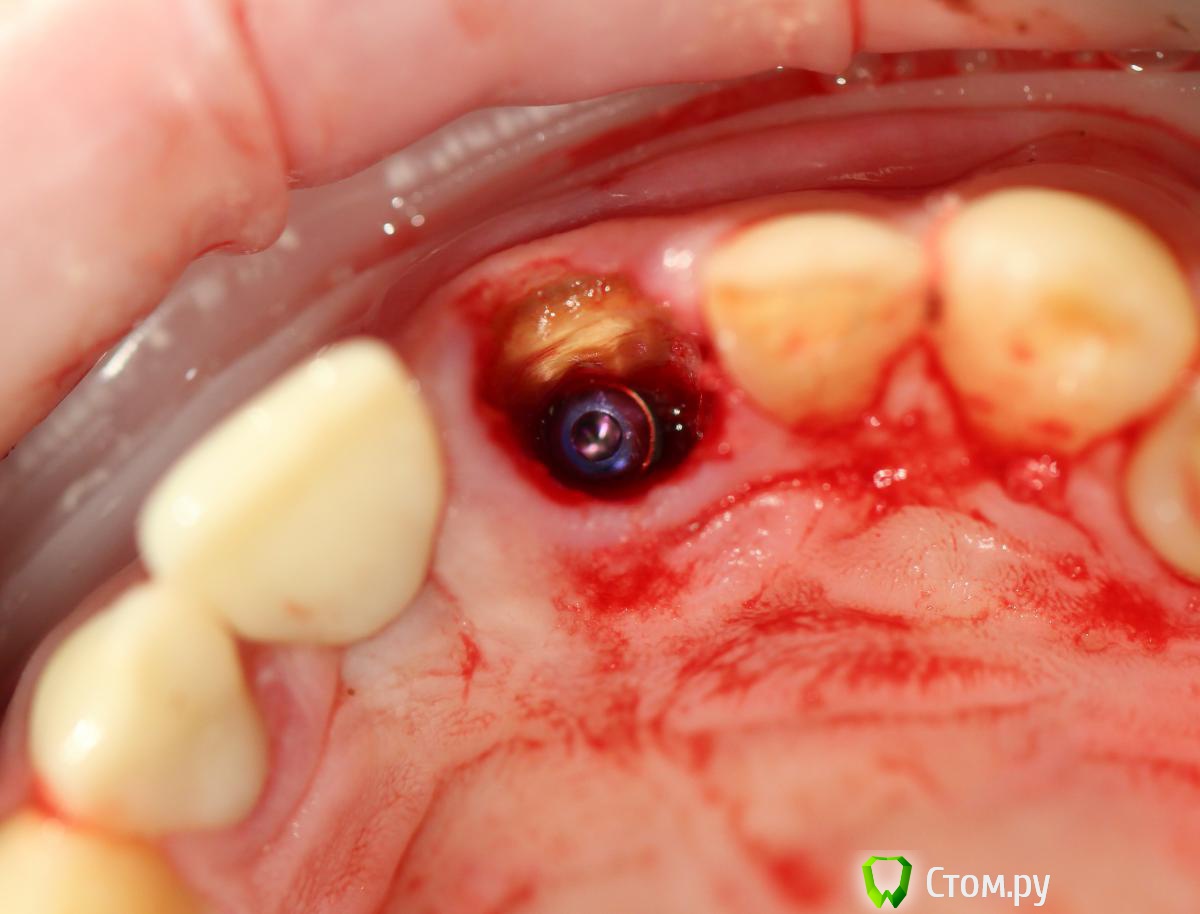

Andex Опубликовано 7 октября, 2014 Поделиться Опубликовано 7 октября, 2014 Внесу свой взгляд на тему. Мне интерестна методика - выкладываю свой кейс. Солидарен с Александром, если Вам интерестно - могу поделиться результатами и наблюдениями своих пациентов. На последнем фото - установил формирователь, тк через неделю после операции разошлись швы и сместился мною плохо мобилизованный ротированный(недостаточно) лоскут с неба - мои навыки еще далеки от идеала. Ссылка на комментарий

kriokov Опубликовано 8 октября, 2014 Поделиться Опубликовано 8 октября, 2014 Солидарен с Александром, если Вам интерестно - могу поделиться результатами и наблюдениями своих пациентов а почему в этом случае отдали предпочтение щитку?Конфигурация гребня хорошая, рядом коронка на болте в хорошем состоянии, вкрутил бы болт немедленно + графт в щель + сст, + врем коронка. ИмХо 2 1 Ссылка на комментарий

Andex Опубликовано 8 октября, 2014 Поделиться Опубликовано 8 октября, 2014 (изменено) а почему в этом случае отдали предпочтение щитку?Конфигурация гребня хорошая, рядом коронка на болте в хорошем состоянии, вкрутил бы болт немедленно + графт в щель + сст, + врем коронка. ИмХоМне понравилась теория данной методики- поэтому я пока отношусь к числу людей,кто верит в щит. Рядом винт - тоже моя работа, сделал специально 2 зуба рядом в одинаковых условиях(на одном пациенте), чтобы динамику в сравнении наглядно вести. Графт+сст+времянка - пока считаю свой уровень недостаточным для таких продвинутых методик, в основном из-за сст,тк не научился еще с ним работать как надо(( Изменено 8 октября, 2014 пользователем Andex 1 Ссылка на комментарий